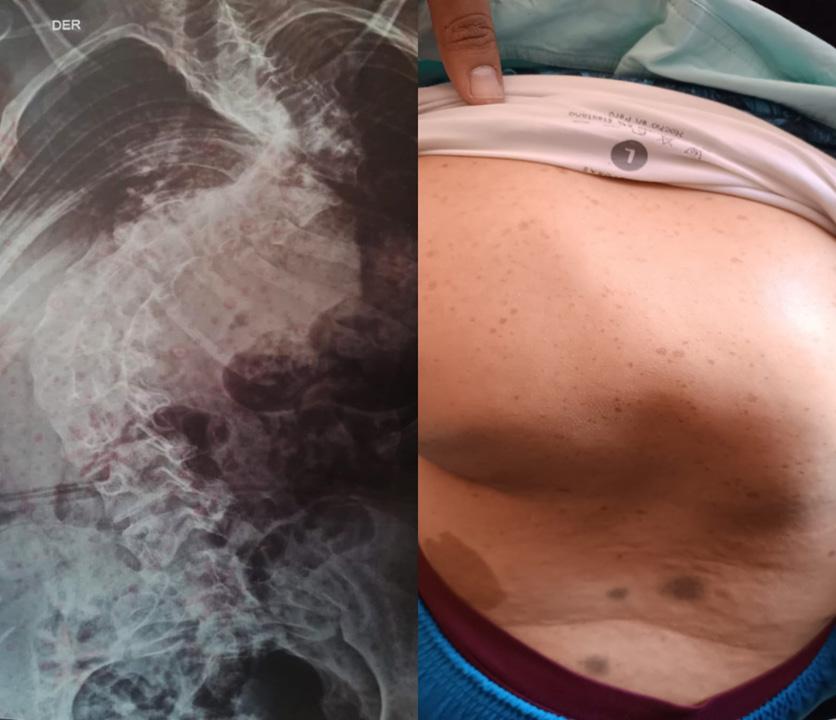

Turn static files into dynamic content formats.

Create a flipbook

Issuu converts static files into: digital portfolios, online yearbooks, online catalogs, digital photo albums and more. Sign up and create your flipbook.